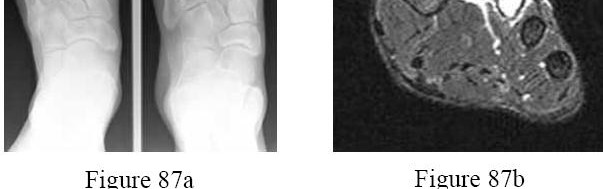

Explanation

Recent high-quality level I evidence (such as the Willits study) has demonstrated that when an early functional rehabilitation protocol (early weight-bearing in a functional brace) is utilized, the re-rupture rate of non-operative management is equivalent to that of operative repair, while completely avoiding surgical risks such as wound breakdown and sural nerve injury.